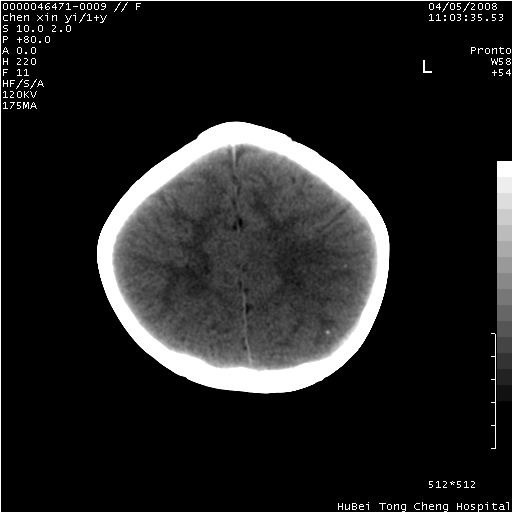

以下是引用zhangzhongshou在2008-4-9 12:54:00的发言:[br]请结合病史,有以下可能1、炎性肉芽肿钙化(含结核)2、寄生虫钙化(含脑囊虫)3、其他良性钙化性病变